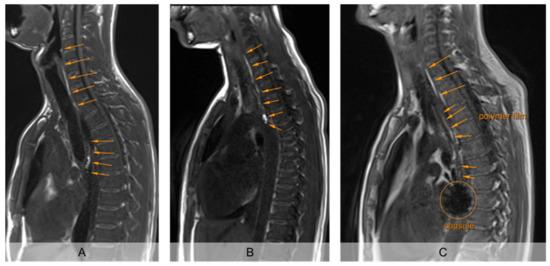

The unrolled PVA film in the esophagus was clearly detectable from the first recording 2 min after intake in strongly T1 weighted MRI, so that its unrolled length was measurable (Figure 2). The mucoadhesive PVA film contrasted by hibiscus tea was clearly visible from the surrounding tissue in all subjects on all days. Moreover, the sinker loaded with iron oxide used in setup B showed a clear signal extinction on MRI, so that the fate of the carrier capsule could also be evaluated (Figure 2C).

Figure 2.

Exemplary representation of sagittal imaging 5 min after application of the EsoCap system. (A): (Almost) completely unrolled film (study setup A, without additional sinker). (B): Incompletely unrolled film, with particularly intense signal of the unrolled film in the capsule (study setup A, without additional sinker). (C): (Nearly) completely unrolled film, using sinker, loaded with iron oxide for signal extinction (study setup B).

Evaluation of the MRI images showed that the average film length unrolled from the EsoCap system on the individual days in setup A without sinker was between 6.5 and 7.1 cm (Figure 3). Thus, approximately 15 cm remained in the capsule, which was visible as a particularly bright spot on the MRI images (Figure 2A,B). In study setup B, on average 9.6 cm, 7.9 cm and 6.8 cm were unrolled, with highest values on day 4. In general, the use of a sinker significantly increased the unrolled length from 6.8 ± 3.9 cm (n = 36) in all administrations in setup A to 8.1 ± 4.1 cm (n = 36) in setup B (paired t-test, p < 0.05). The iron oxide-loaded sinker made it particularly easy to localize the capsule in the subject and to evaluate the unrolled film length.